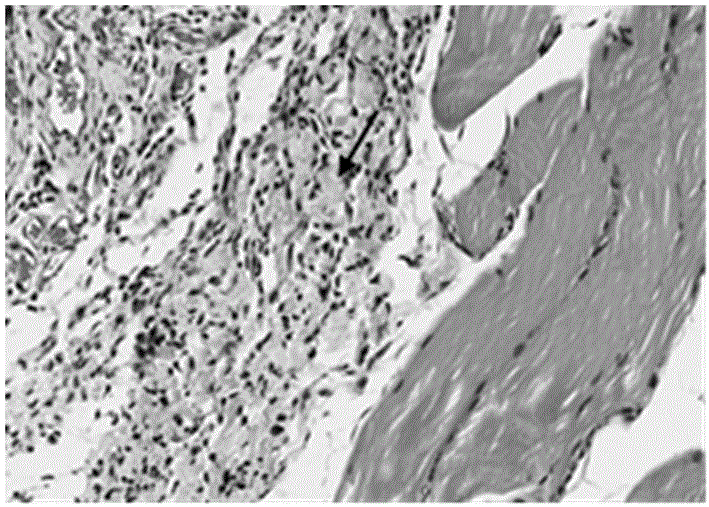

构建大鼠大动脉损伤出血动物模型的方法及在止血材料评价体系中的应用